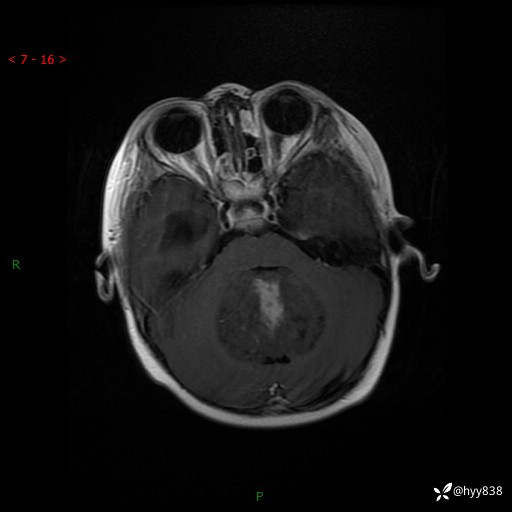

性别:女

年龄:3岁

简要病史:发现行走不稳2个月,加重1个月

颅脑MRI平扫+增强